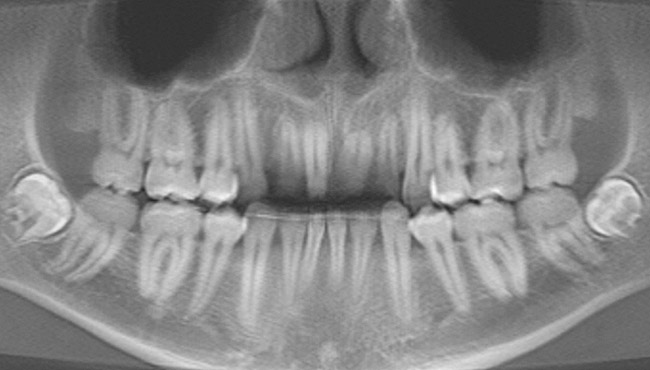

Figure 22  Case Three Preoperative panoramic view.

Figure 22

A 24-year-old non-smoking man presented for treatment of a horizontally fractured left central incisor (Figure 21 and Figure 22). The patient requested to have an implant placed to replace the left central incisor as to not have any damage to the adjacent dentition.

Complicating the treatment site was the apically positioned facial height of contour at the left central incisor, and the adjacent left lateral incisor (Figure 21.) Additional sites of recession were present throughout the oral cavity and were to be addressed by the tunnel grafting procedure previously outlined.